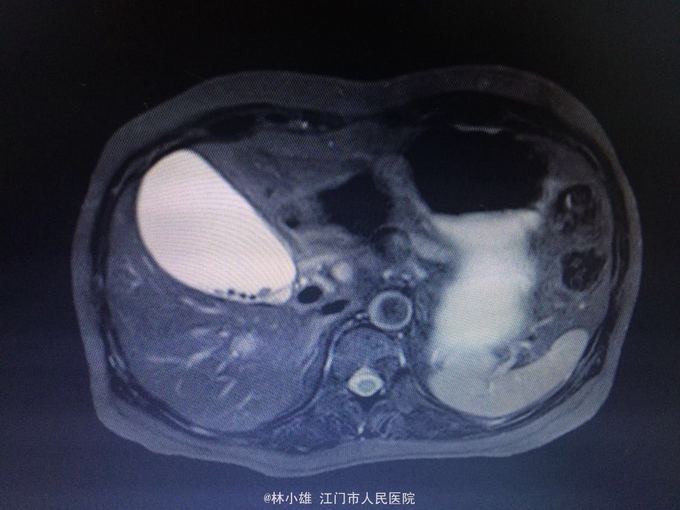

55岁女性,既往体健。 腹痛1次,腹胀1月,身目黄染20余天。 1月前突发腹痛1次,持续性胀痛,止痛治疗好转。次日出现腹胀、乏力,予胃药治疗2天无效后停药。20余天前出现身目黄染,尿黄,至当地医院查胆红素升高,以直胆为主,查腹部CT示胆囊结石,肝内外胆管无扩张,考虑毛细胆管炎,激素冲击3天、护肝退黄治疗无好转,遂入院。大便正常。

查体:皮肤巩膜重度黄染,腹软,无压痛及反跳痛,肝区叩痛阴性,肝脾未及,移动性浊音-。 入院查:凝血、铜蓝蛋白、肿瘤指标、乙肝两对半、甲戊丙肝抗体、自免肝抗体、体液免疫均未见异常。

梗阻性黄疸:毛细胆管炎? 予利胆退黄治疗,请外科会诊暂不考虑外科疾病所致,建议继续内科积极治疗。

复查彩超肝脏同前。 患者肝内外胆管无明显扩张,各项指标支持肝内胆汁淤积可能,考虑毛细胆管炎,积极内科治疗黄疸无明显缓解,建议激素治疗,但患者家属拒绝,要求转院治疗。